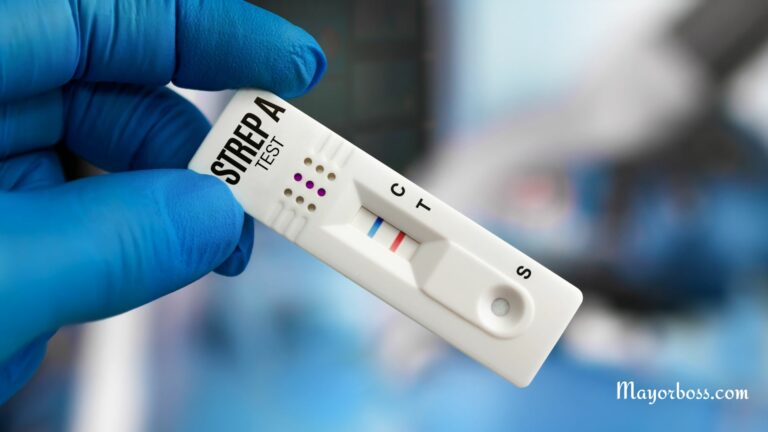

Can You Get a Strep Test at Walgreens?

Have you ever woken up with a sore…